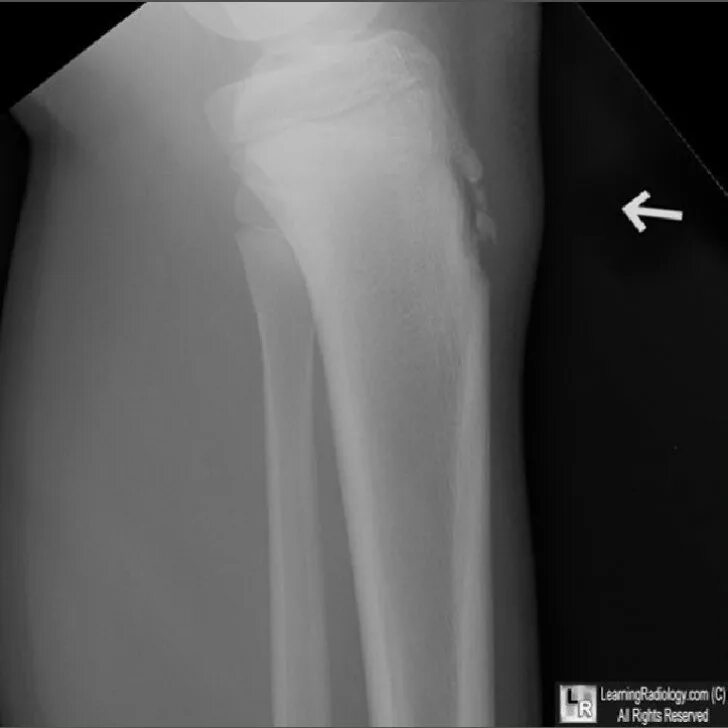

Болезнь осгут шляттера